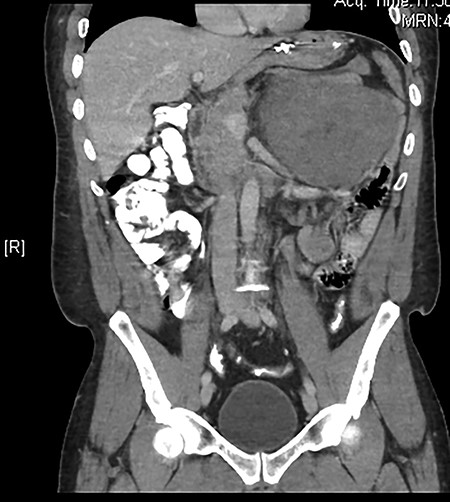

The results of routine blood investigations were within normal limits and an abdominal X-ray showed a normal bowel gas pattern. An abdominal computed tomography (CT) scan showed a huge, well-defined, inhomogeneous mass at the left hypochondrium measuring about 15.8 × 14.6 × 12.8 cm (Fig. 1). No signs of bowel distension or obstruction were observed. Magnetic resonance imaging showed that the mass and liver were metastasis-free. An esophagogastroduodenoscopy revealed a 1-cm smooth lesion in the mid-esophagus, which was positive for desmin and negative for CD117, with smooth muscle differentiation (most likely a leiomyoma). A colonoscopy revealed two hyperplastic rectosigmoid polyps, which were negative for malignancy or dysplasia. A provisional diagnosis was made for gastrointestinal stromal tumor.

A computed tomography (CT) scan showed a well-defined, inhomogeneous mass at the left hypochondrium displacing the stomach, colon, and nearby organs.